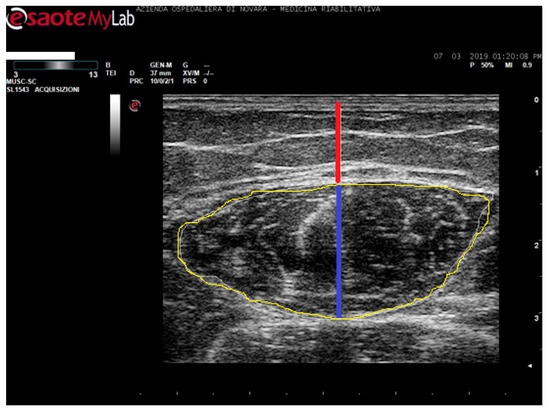

Rectus Femoris Characteristics in Post Stroke Spasticity: Clinical Implications from Ultrasonographic Evaluation

5. Materials and Methods